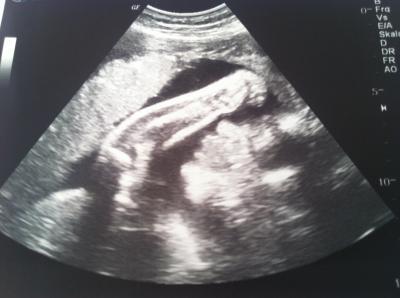

Ich hatte heute nach langen 2 Monaten auch wieder einen Ultraschall. Meine kleine Knutschkugel hat sich die ganze Zeit von seiner Schokoladenseite gezeigt und die Lippen gespitzt und Knutschmünder geformt :) Sah auf dem Bildschirm noch besser aus, als auf dem Foto. Der Kleine hat sich, nachdem er fast immer nur quer lag zum 1.Mal jetzt auch mit dem Köpfchen nach unten gedreht. Yieppieh. Jetzt muss er nur noch da bleiben. Der FA meinte, dass es ein propper Kind ist mit im Moment 1.500 g und eher 6 Tage weiter, hat aber den ET nicht korrigiert. Und wir sollen uns auf einen großen Kopf einstellen